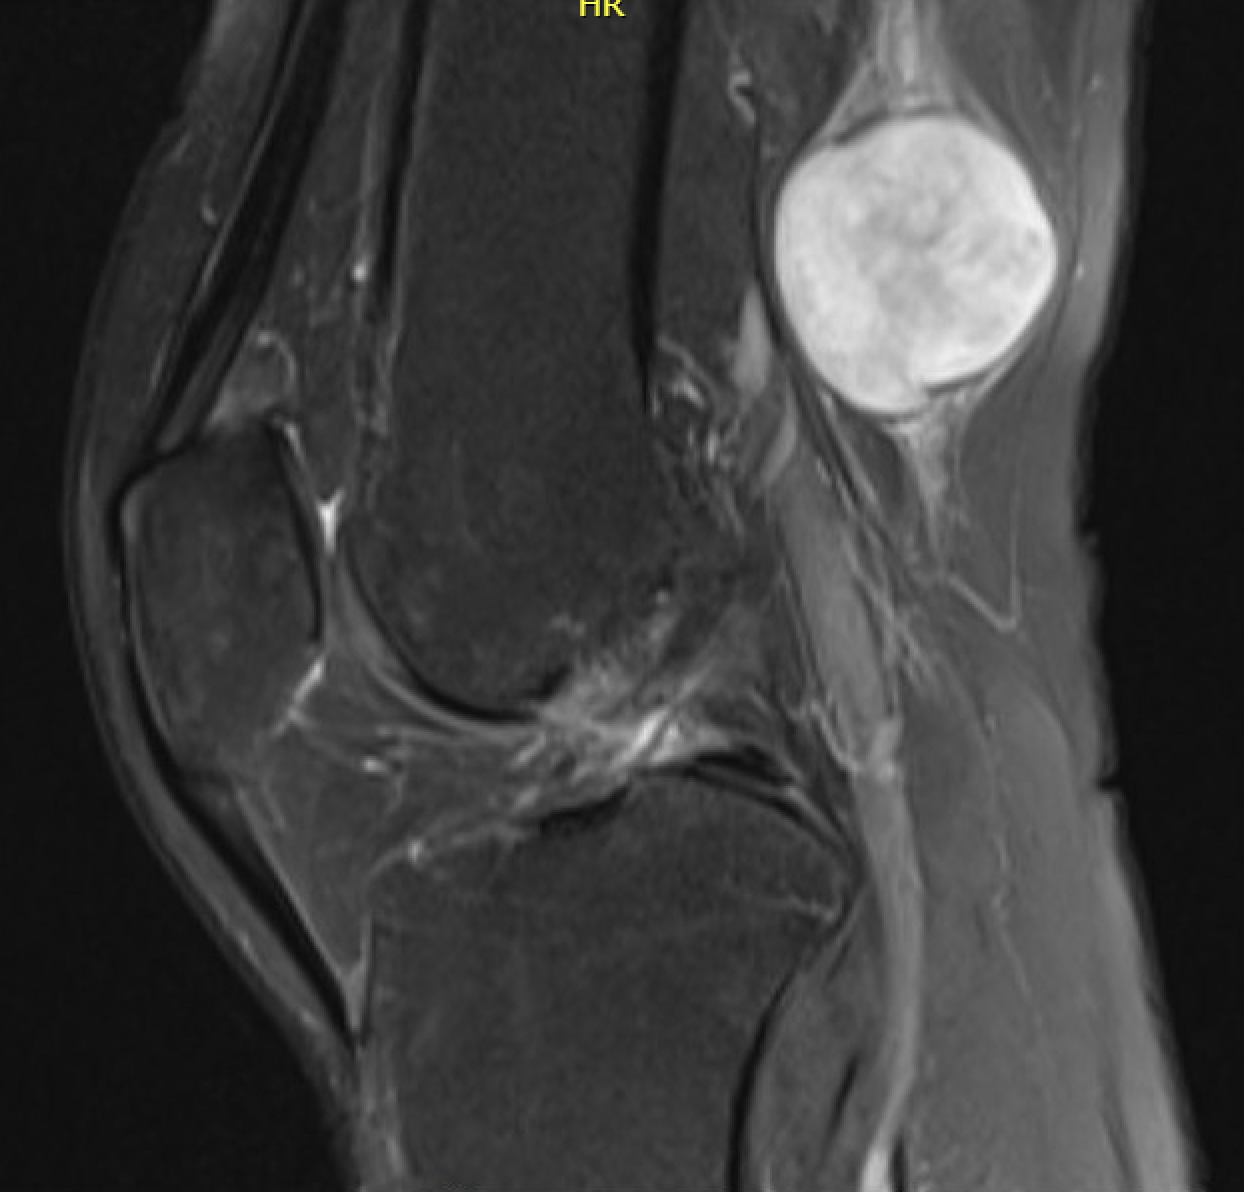

MRI

Target sign

- hypointense centrally

- hyperintense peripherally

Neurofibroma common peroneal nerve